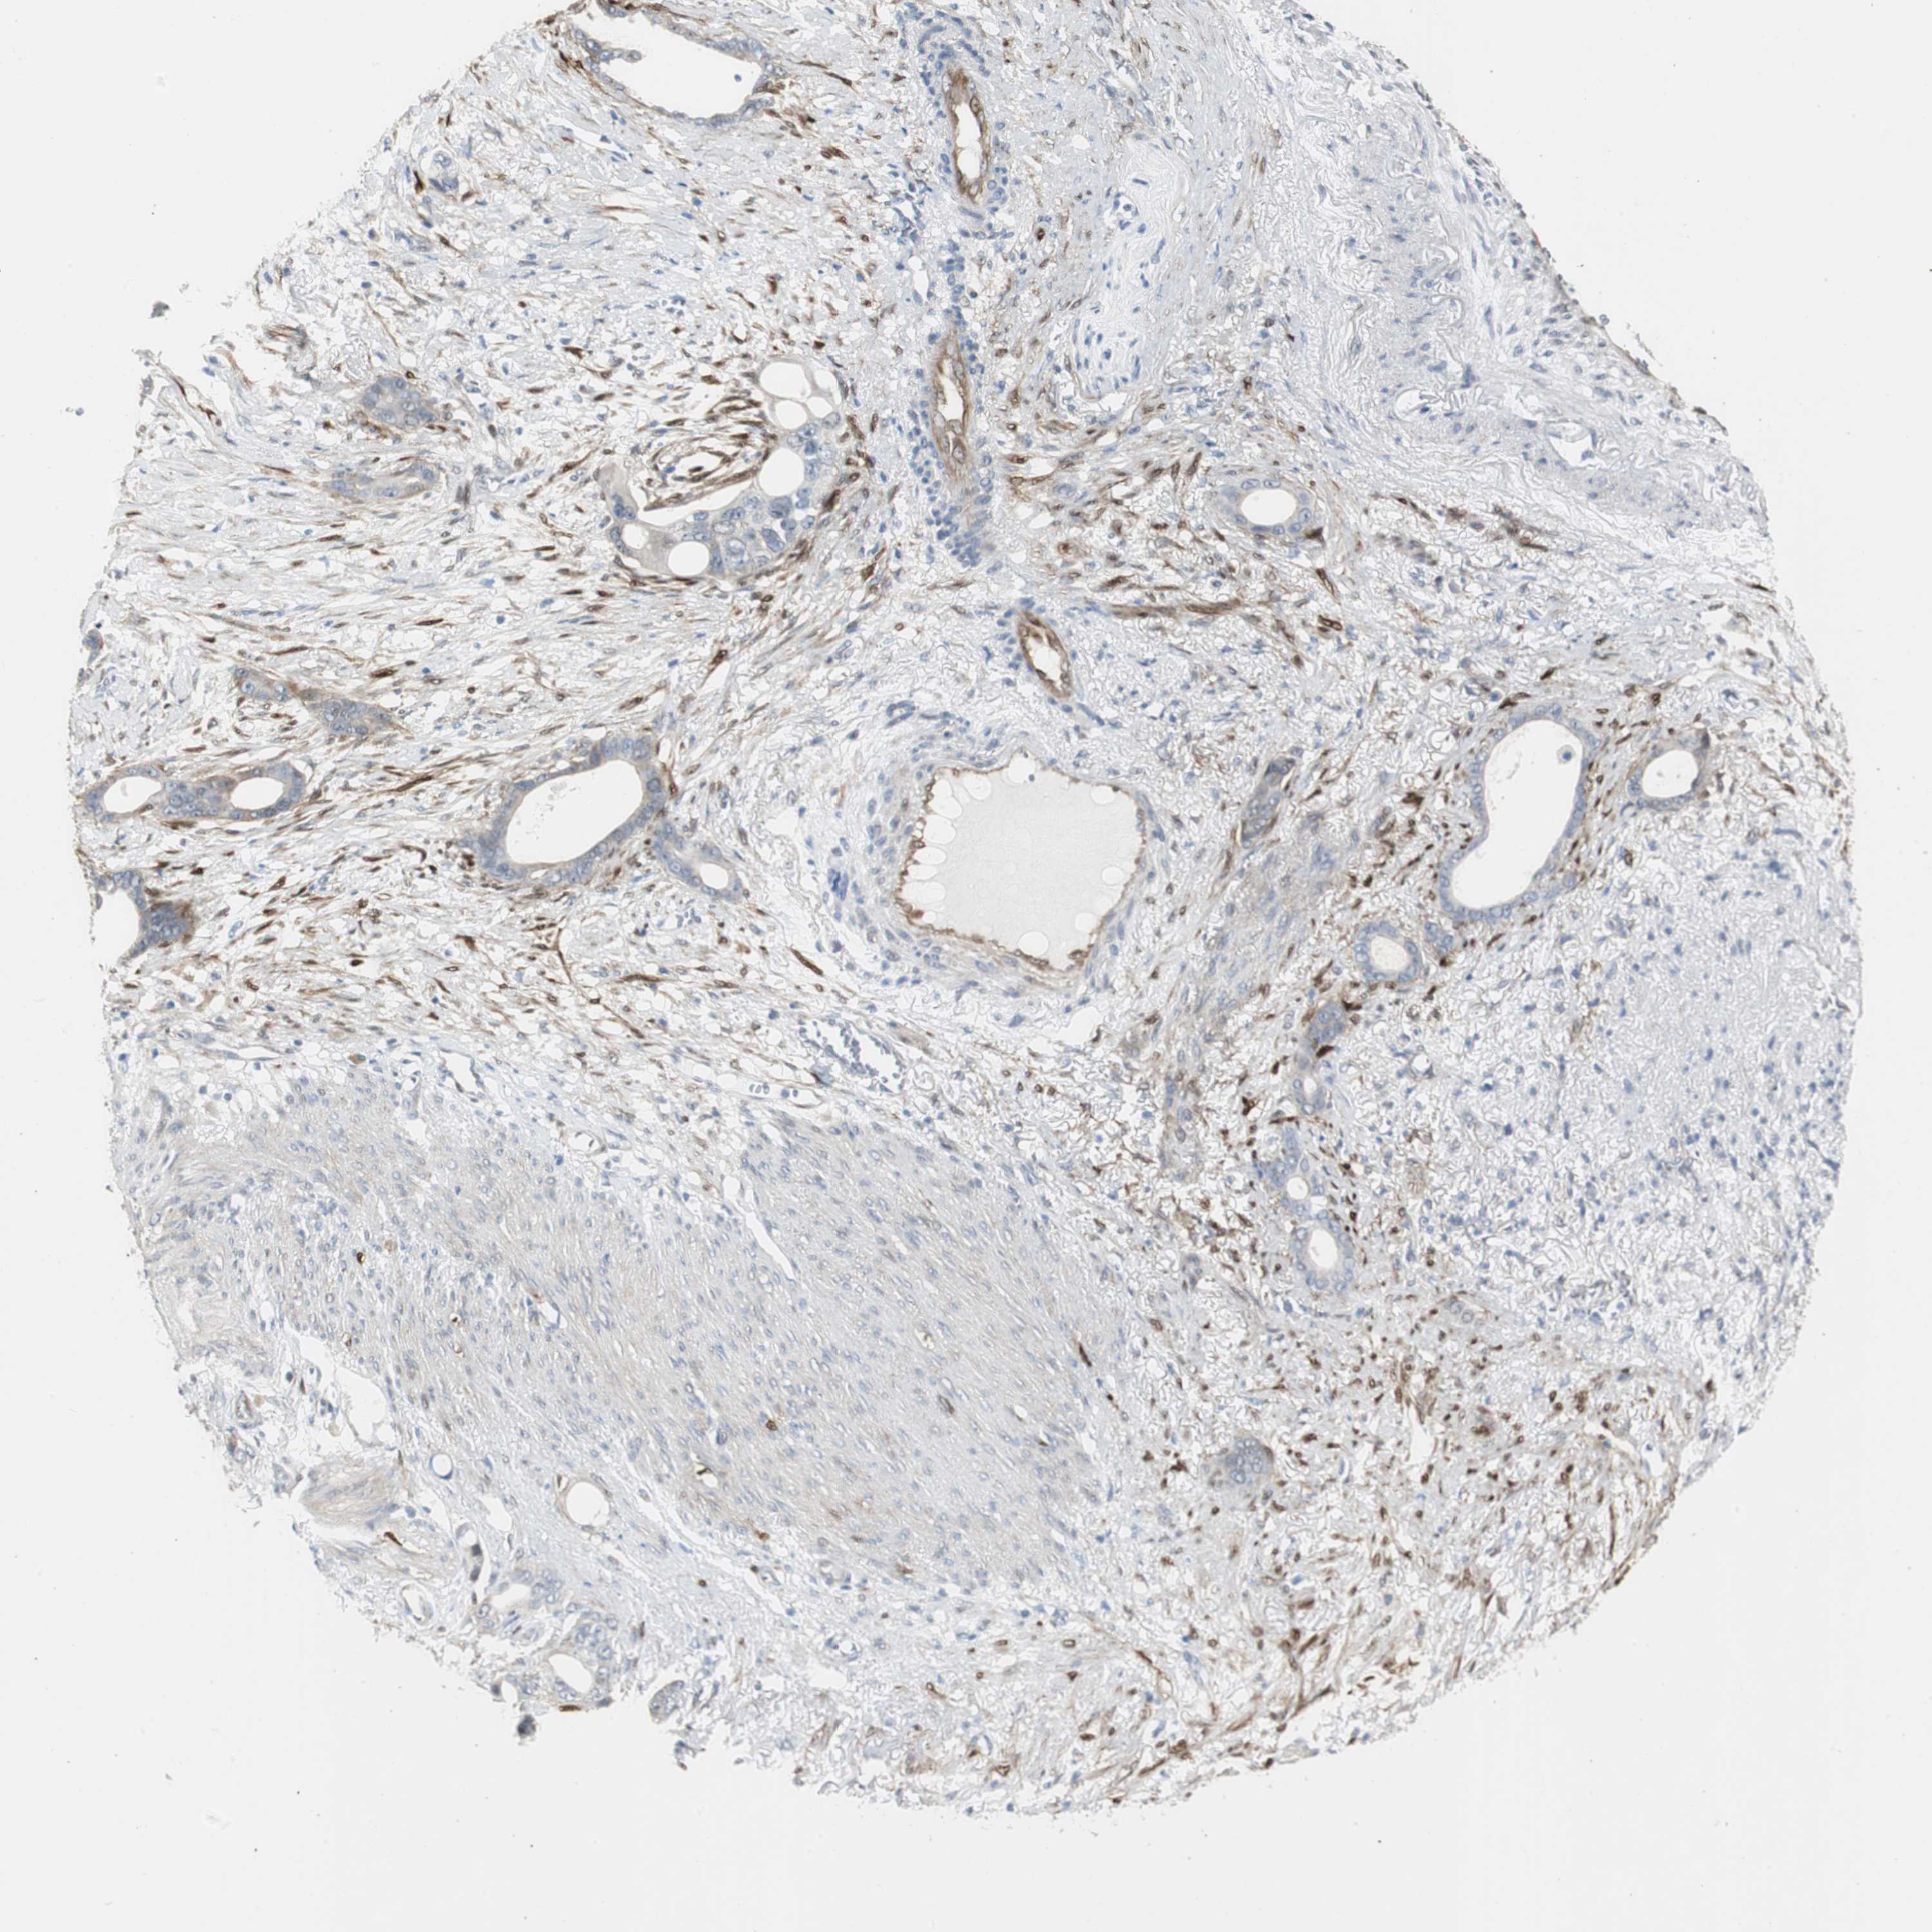

STOMACH CANCER - Protein expressioni

A mouse-over function shows sample information and annotation data. Click on an image to view it in a full screen mode. Samples can be filtered based on level of antibody staining by selecting one or several of the following categories: high, medium, low and not detected. The assay and annotation is described here.

Antibody stainingi

Antibody staining in the annotated cell types in the current human tissue is reported as not detected, low, medium, or high, based on conventional immunohistochemistry profiling in selected tissues. This score is based on the combination of the staining intensity and fraction of stained cells.

Each image is clickable and will lead to virtual microscopy that enables deeper exploration of all samples and also displays staining intensity scores, fraction scores and subcellular localization as well as patient and tissue information for each sample.

Antibody HPA005922

Antibody HPA006028

Antibody CAB008368

Staining

High

Medium

Low

Not detected

Intensity

Strong

Moderate

Weak

Negative

Quantity

>75%

75%-25%

<25%

None

Location

Nuclear

Cytoplasmic/membranous

Cytoplasmic/membranous,nuclear

Adenocarcinoma, NOS

Adenocarcinoma, High grade